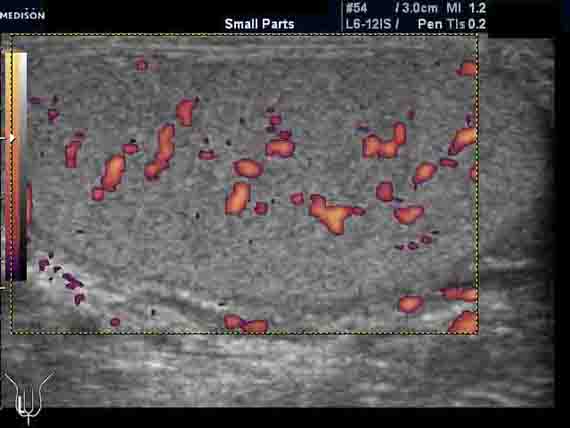

Усиление сосудистого рисунка яичек.

Пациент 42 лет. Направлен на УЗИ мошонки с подозрением на небольшую кисту в придатке яичка. Жалоб нет. Анамнез без особенностей. Пальпаторно мошонка в норме.

При УЗИ киста не обнаружена. Выявляются небольшая неоднородность структуры яичек (изменения незначительные) и заметное усиление сосудистого рисунка (до 11-12 срезов сосудов в скане). Другой патологии нет. Форма и размеры яичек нормальные. Придатки яичек не изменены. Признаков гидроцеле и ваникоцеле нет.

Вопрос: в чем причина заметного усиления сосудистого рисунка яичек?